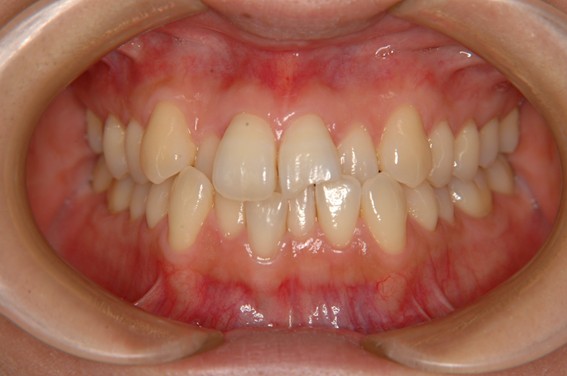

| 主訴 | 前歯が逆に噛んでいるところがある。歯のがたつき。 |

| 治療内容 | 表側ワイヤー矯正、4本抜歯を行いました。 |

| 治療費 | 880,000円+ダイレクトボンディング33,000円(税込) |

| 治療期間 | 30ヶ月 |

| 治療回数 | 30回 |

| 想定されたリスク | 歯根吸収、歯髄壊死、歯髄充血、歯肉退縮のリスクがありました。 |